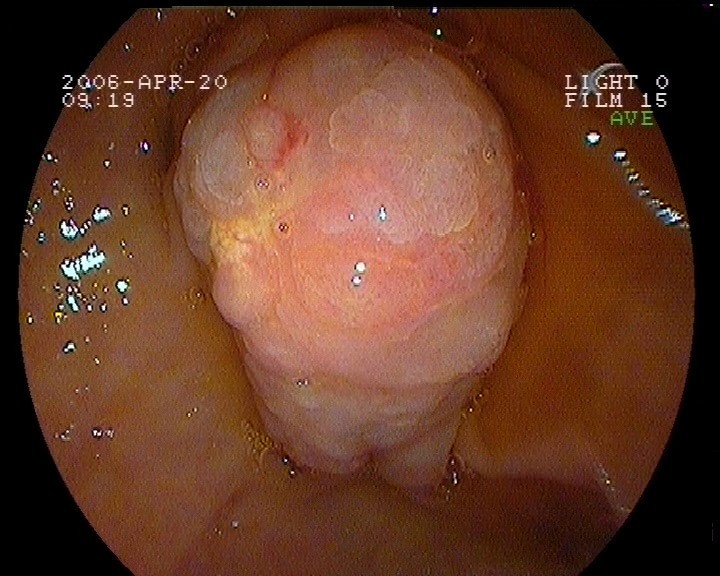

Gastroskopie - Magenkarzinom